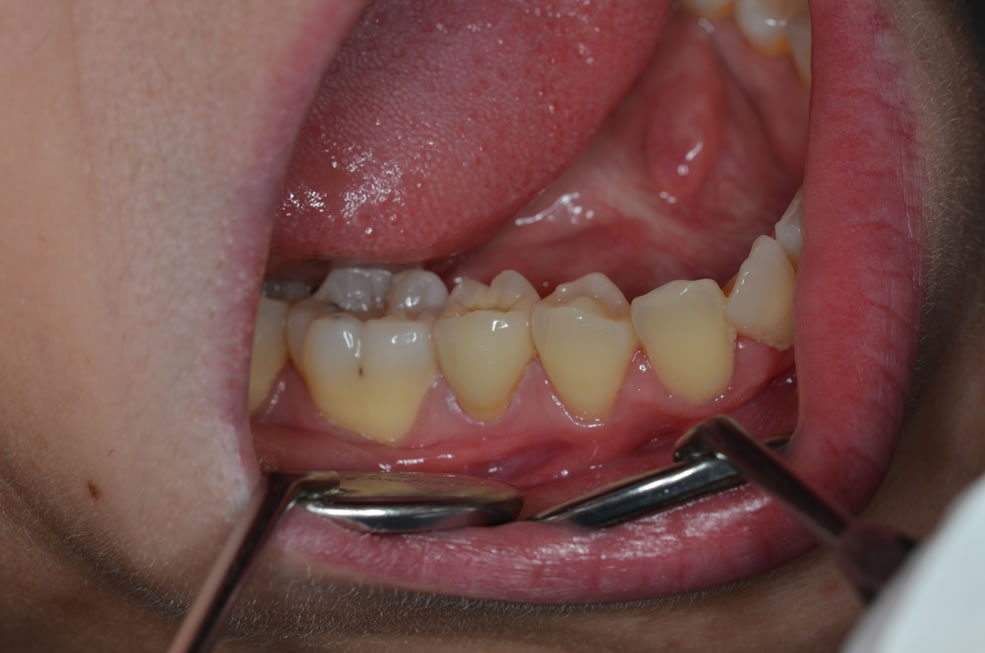

Cas clinique N°1 : overlay Emax sur 14

Cas clinique N°2 onlay Emax sur 36 :

Cas clinique N°1 : Couronne Emax stratifiée sur 26